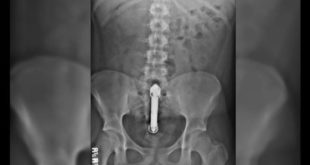

Read More »Hombre de 50 años de edad sale corriendo desnudo por la calle por esta dolorosa y penosa razón

Un hombre, de unos 50 años y totalmente desnudo, vivió momentos críticos luego que un consolador se le trabara en su trasero. El hecho se registró en Avenida Balbín y Crisólogo Larralde, Argentina. Según los testigos, el hombre salió a la calle desnudo pidiendo ayuda a gritos. Con la policía …